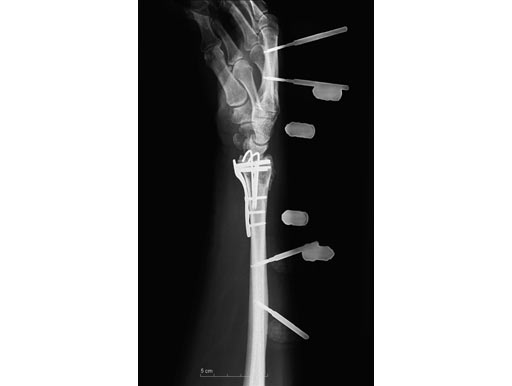

54-year-old female with 23-C3 fracture after fall

External fixator due to severe soft-tissue trauma. Palmar plate 1 week later. .